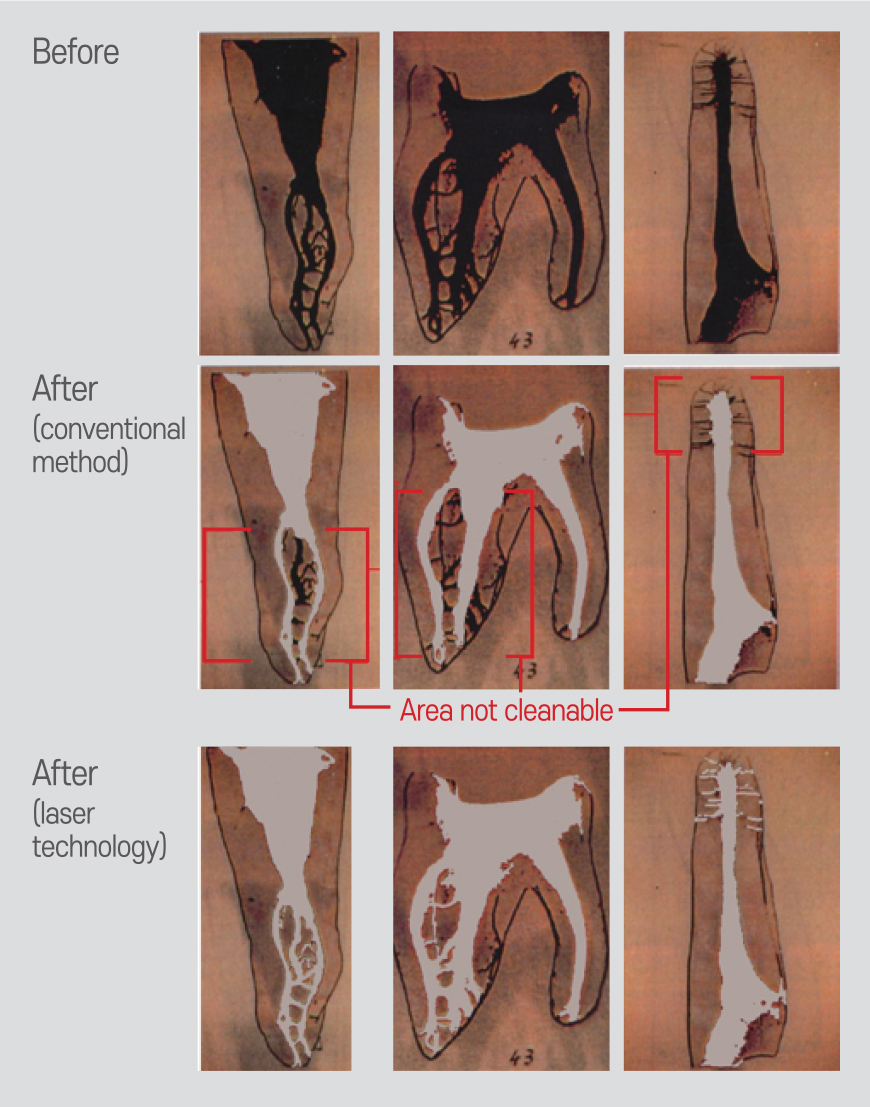

Endo, Re-Endo, Pulpotomy, Apicoectomy

- Excellent debridement and sterilization minimize recurrence

- 10x deeper penetration than chemicals, sterilizing even accessory canals

- Simple and quick procedure

Debris removal and sterilization inside the canal with just 2–3 minutes of laser irradiation per canal

- Minimally invasive approach

Allows necessary canal enlargement without damaging the root or causing unnecessary widening or weakening